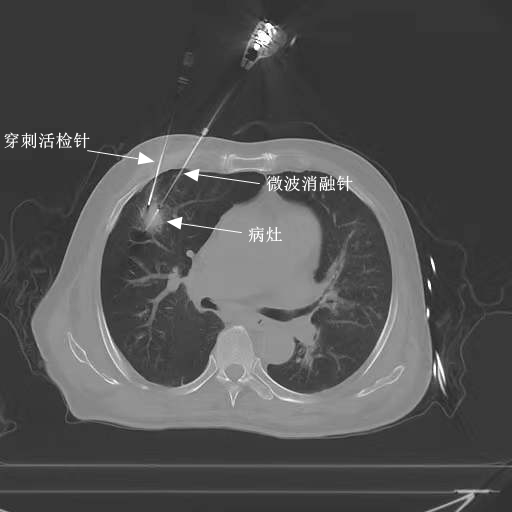

手术当天,副主任医师许猛军和住院医师徐赫遥严格按照手术计划实施手术,在主管技师刘枫,副主任护师、护士长向代敏等团队成员的通力协作下,将微波消融针准确送达病灶,先行5分钟的消融治疗,接着活检针穿刺到病灶内部,成功取材2条完整组织条,然后消融针调针后继续实施4分钟消融,治疗顺利结束。

患者术中CT图像

在拔除消融针及活检针的时候,还是出现了预判到的气胸。通过与胸外科主任医师陆源建沟通讨论,考虑到患者非常差的肺功能和较弱的代偿能力,请胸外科陆源建团队实施标准管径的胸腔闭式引流术。